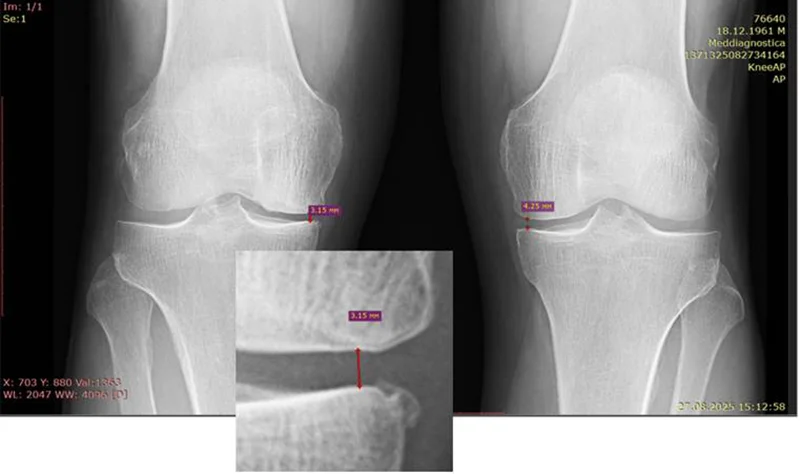

В Центрі вдалося зупинити розвиток артрозу коліна і навіть збільшити висоту суглобової щилина на 22% (від 2.80 мм до 3.98мм).

Стан суглобової щілини після 27 днів лікування (контроль 27.08.2025).

Ситуація змінилася лише тоді, коли він звернувся до нашого Центру. Біль став турбувати з кожним днем рідше. Вже через 27 днів лікування ми отримали рентгенівське підтвердження покращення – збільшення суглобової щилини та зменшення ознак артрозу завдяки спеціально розробленим методам впливу на тканини суглоба.